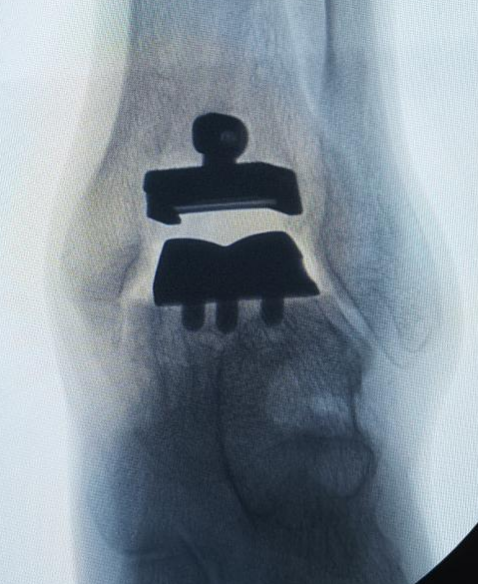

兰大二院骨科开展甘肃省内首例3D打印导航下国产全踝关节置换手术

近日,兰大二院成功为一名踝关节骨性关节炎患者实施3D打印导航下的国产全踝关节置换手术,填补了甘肃省内足踝外科领域的技术空白,为甘肃省及周边地区的广大患者带来了福音。

患者男性、54岁,常年因踝关节慢性疼痛而困扰,曾就诊多家医院无果,病情逐渐加重,已经严重影响患者的运动功能和生活质量。遂来兰大二院骨科就诊。骨科四病区副主任医师王凯接诊后立即完善相关检查明确诊断。结合病人的实际情况经科室讨论后,选择3D打印导航下的国产全踝关节手术治疗方案,在病区主任刘京升的指导下,为患者实施了手术治疗,术后恢复良好,现已康复出院。